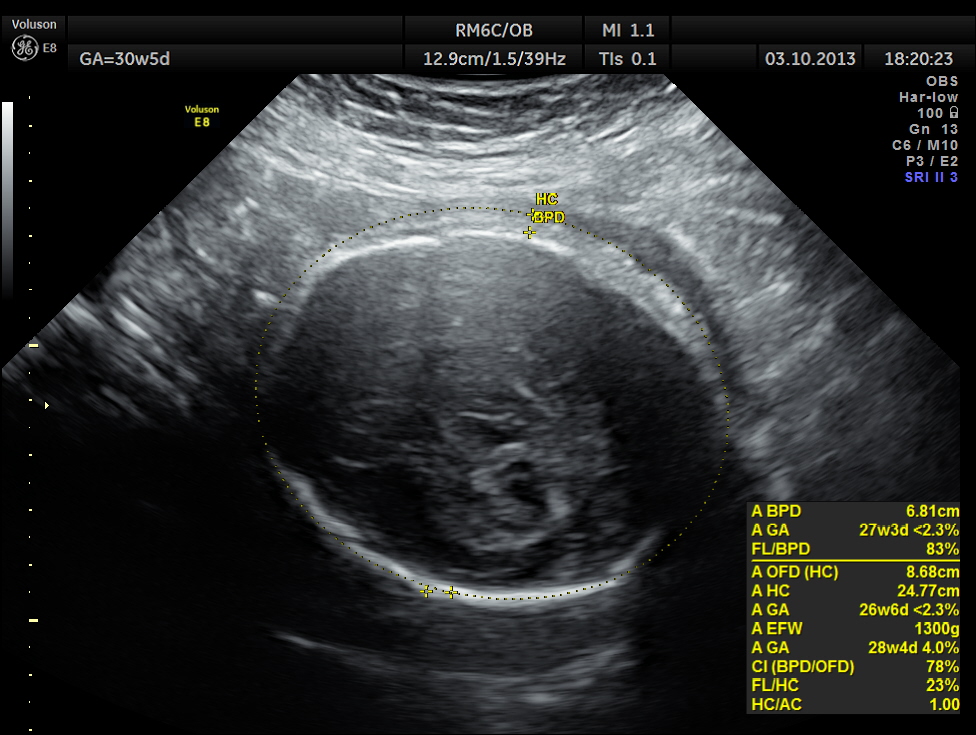

BPD AND HC < 2.3 % TILE suggestive of microcephaly. AC 6.2 % TILE suggestive of growth restriction.

The cerebellum shows 32.1 % tile growth.